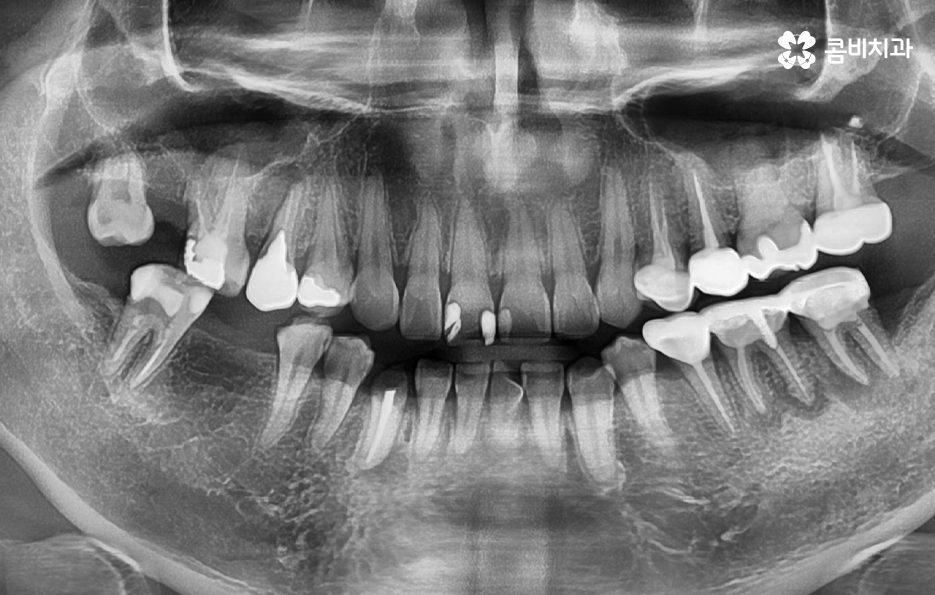

위 사진에서 보시는 충치 단계 처럼 이미 치아의 뿌리 쪽 가까이 까지 충치가 진행된 경우에는 자연치아를 살릴 수 있는지 여부가 치아의 잔존하는 정도에 따라서 달라질 수 있기 때문에 신경치료를 하느냐 마느냐의 문제를 넘어서 치아를 살릴 수 있는지 치아 보존의 기로에 있을 수도 있어요

보통 치아 내부까지 충치가 진행되는 사례는 한번도 치료 받지 않은 치아에서 한번에 치아 뿌리 쪽까지 충치가 진행되기는 보편적으로 힘든 편인데 그 이전에 이미 이가 시리고 통증이 심하기 때문에 자각증상으로도 눈치 챌 수 밖에 없을 거예요

물론 이미 신경이 죽었거나 치아 뿌리 쪽에 염증이 시작되어 통증이 거의 없이 치아의 손상이 커지는 예외적인 사항도 있긴 하지만 보편적으로는 이미 치료를 받았던 레진, 인레이, 크라운 내부에서 2차 충치가 진행되어 치아의 내부까지 심하게 충치가 진행되는 사례가 중년이후에 좀더 많다고 볼 수 있어요

위 사진도 마찬가지로 치석이 상당히 많이 치아 뿌리 쪽 부터 잇몸 까지 쌓여 있는 것을 알 수 있는데요. 충치 단계를 단순히 법랑질 부터 상아질로 깊어지고 치수염 까지 진행되는 큰 가이드라인 만으로는 성인 이후 특히 중년이후부터 발생되고 있는 오래된 보철물로 인한 2차 충치나 치아 사이에서 발생되는 인접면 충치 치료에 있어서 예방이나 초기 치료에 미흡하여 치아 상실로 이어지는 사례를 자주 목격하고 있는데요